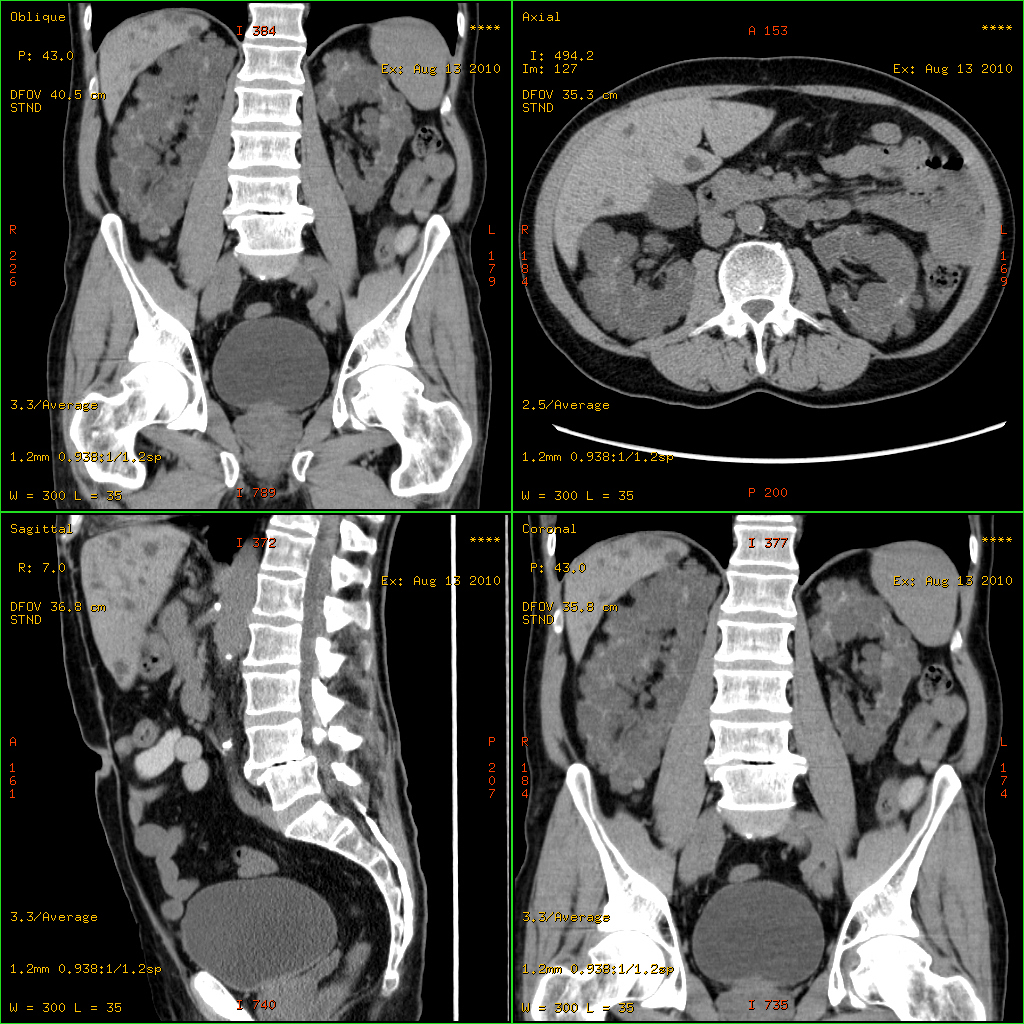

다낭성 신장 질환은 복부 CT 스캔, MRI, 초음파 검사 등을 통해 진단할 수 있다.[22] 신체 검사에서는 비대해진 간, 심잡음, 상승된 혈압 등이 확인될 수 있다.[8]

4. 1. 영상 검사

초음파 검사, CT 스캔, MRI 등의 영상 검사를 통해 다낭성 신장 질환을 확인할 수 있다.[22] 이를 통해 신장에 낭종이 있는지, 낭종의 크기와 개수는 어떻게 되는지 등을 알 수 있다. 신체 검사에서는 비대해진 간, 심잡음, 상승된 혈압 등이 확인될 수 있다.[8]4. 2. 유전자 검사